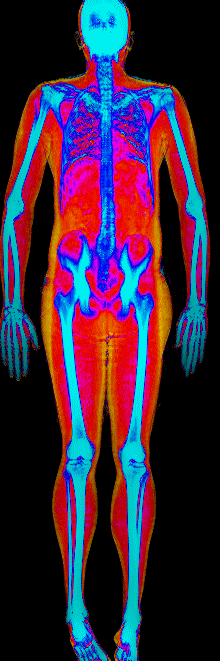

What Fat Loss Looks Like on a DEXA Scan

Lost 30.2 lb of fat, gained 3.9 lb lean · 240 → 214 lb · Age 43

Lost 27.9 lb of fat · 225 → 191 lb · Age 40

Lost 23.7 lb of fat · 186 → 155 lb · Age 34